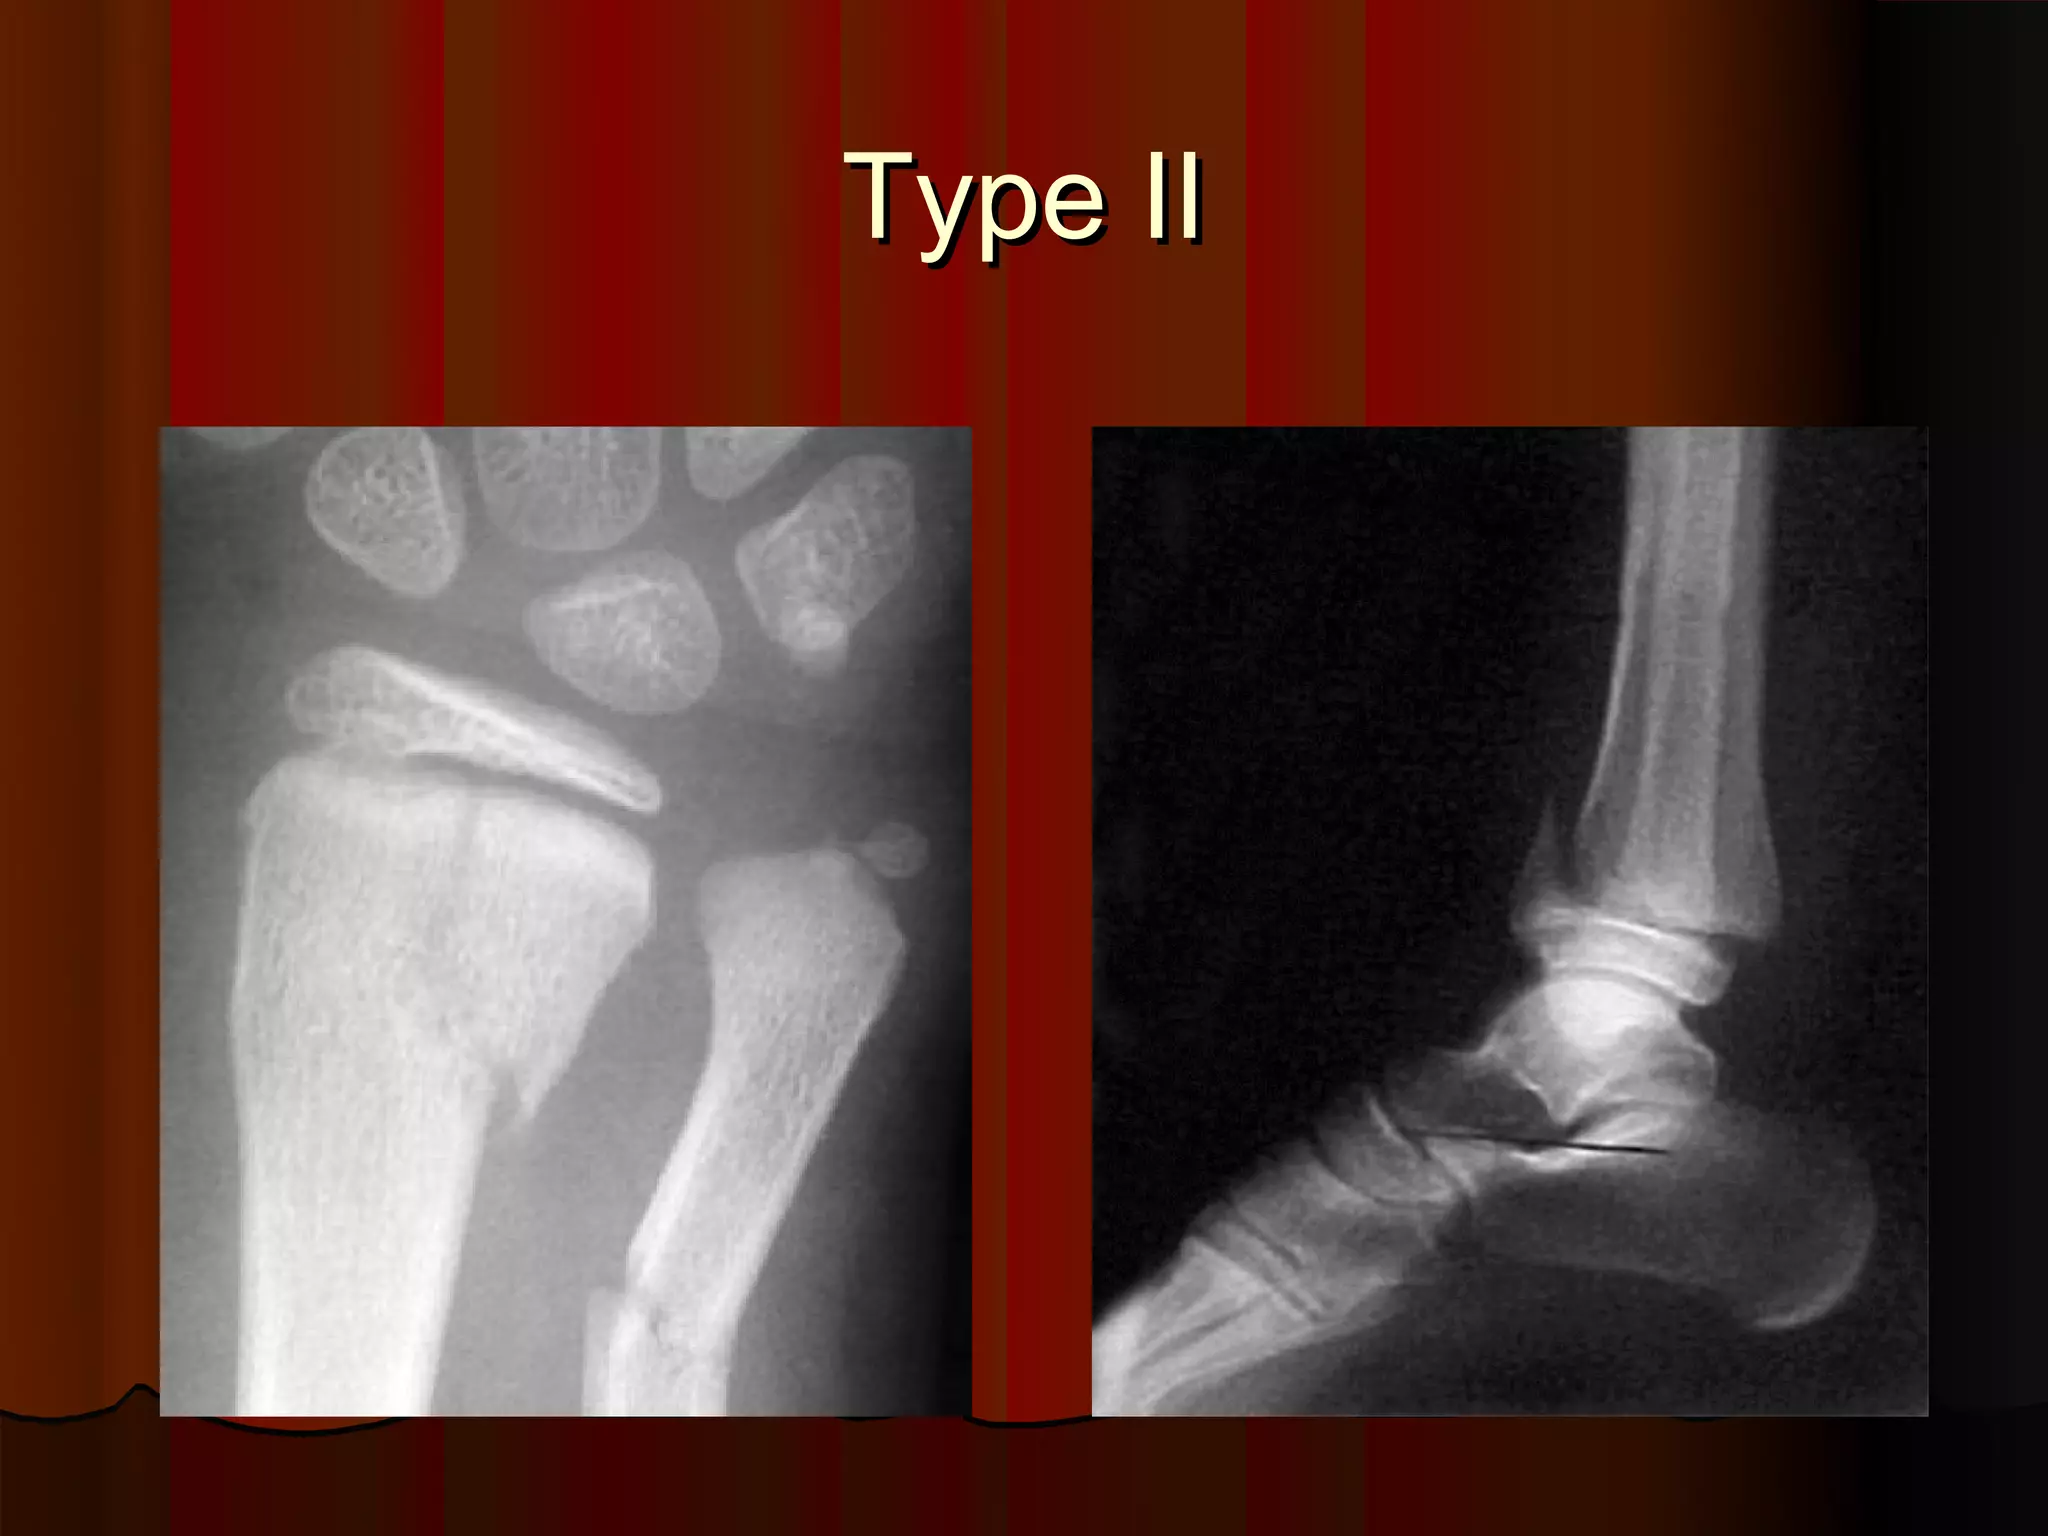

Description of Salter-Harris Type II injury.